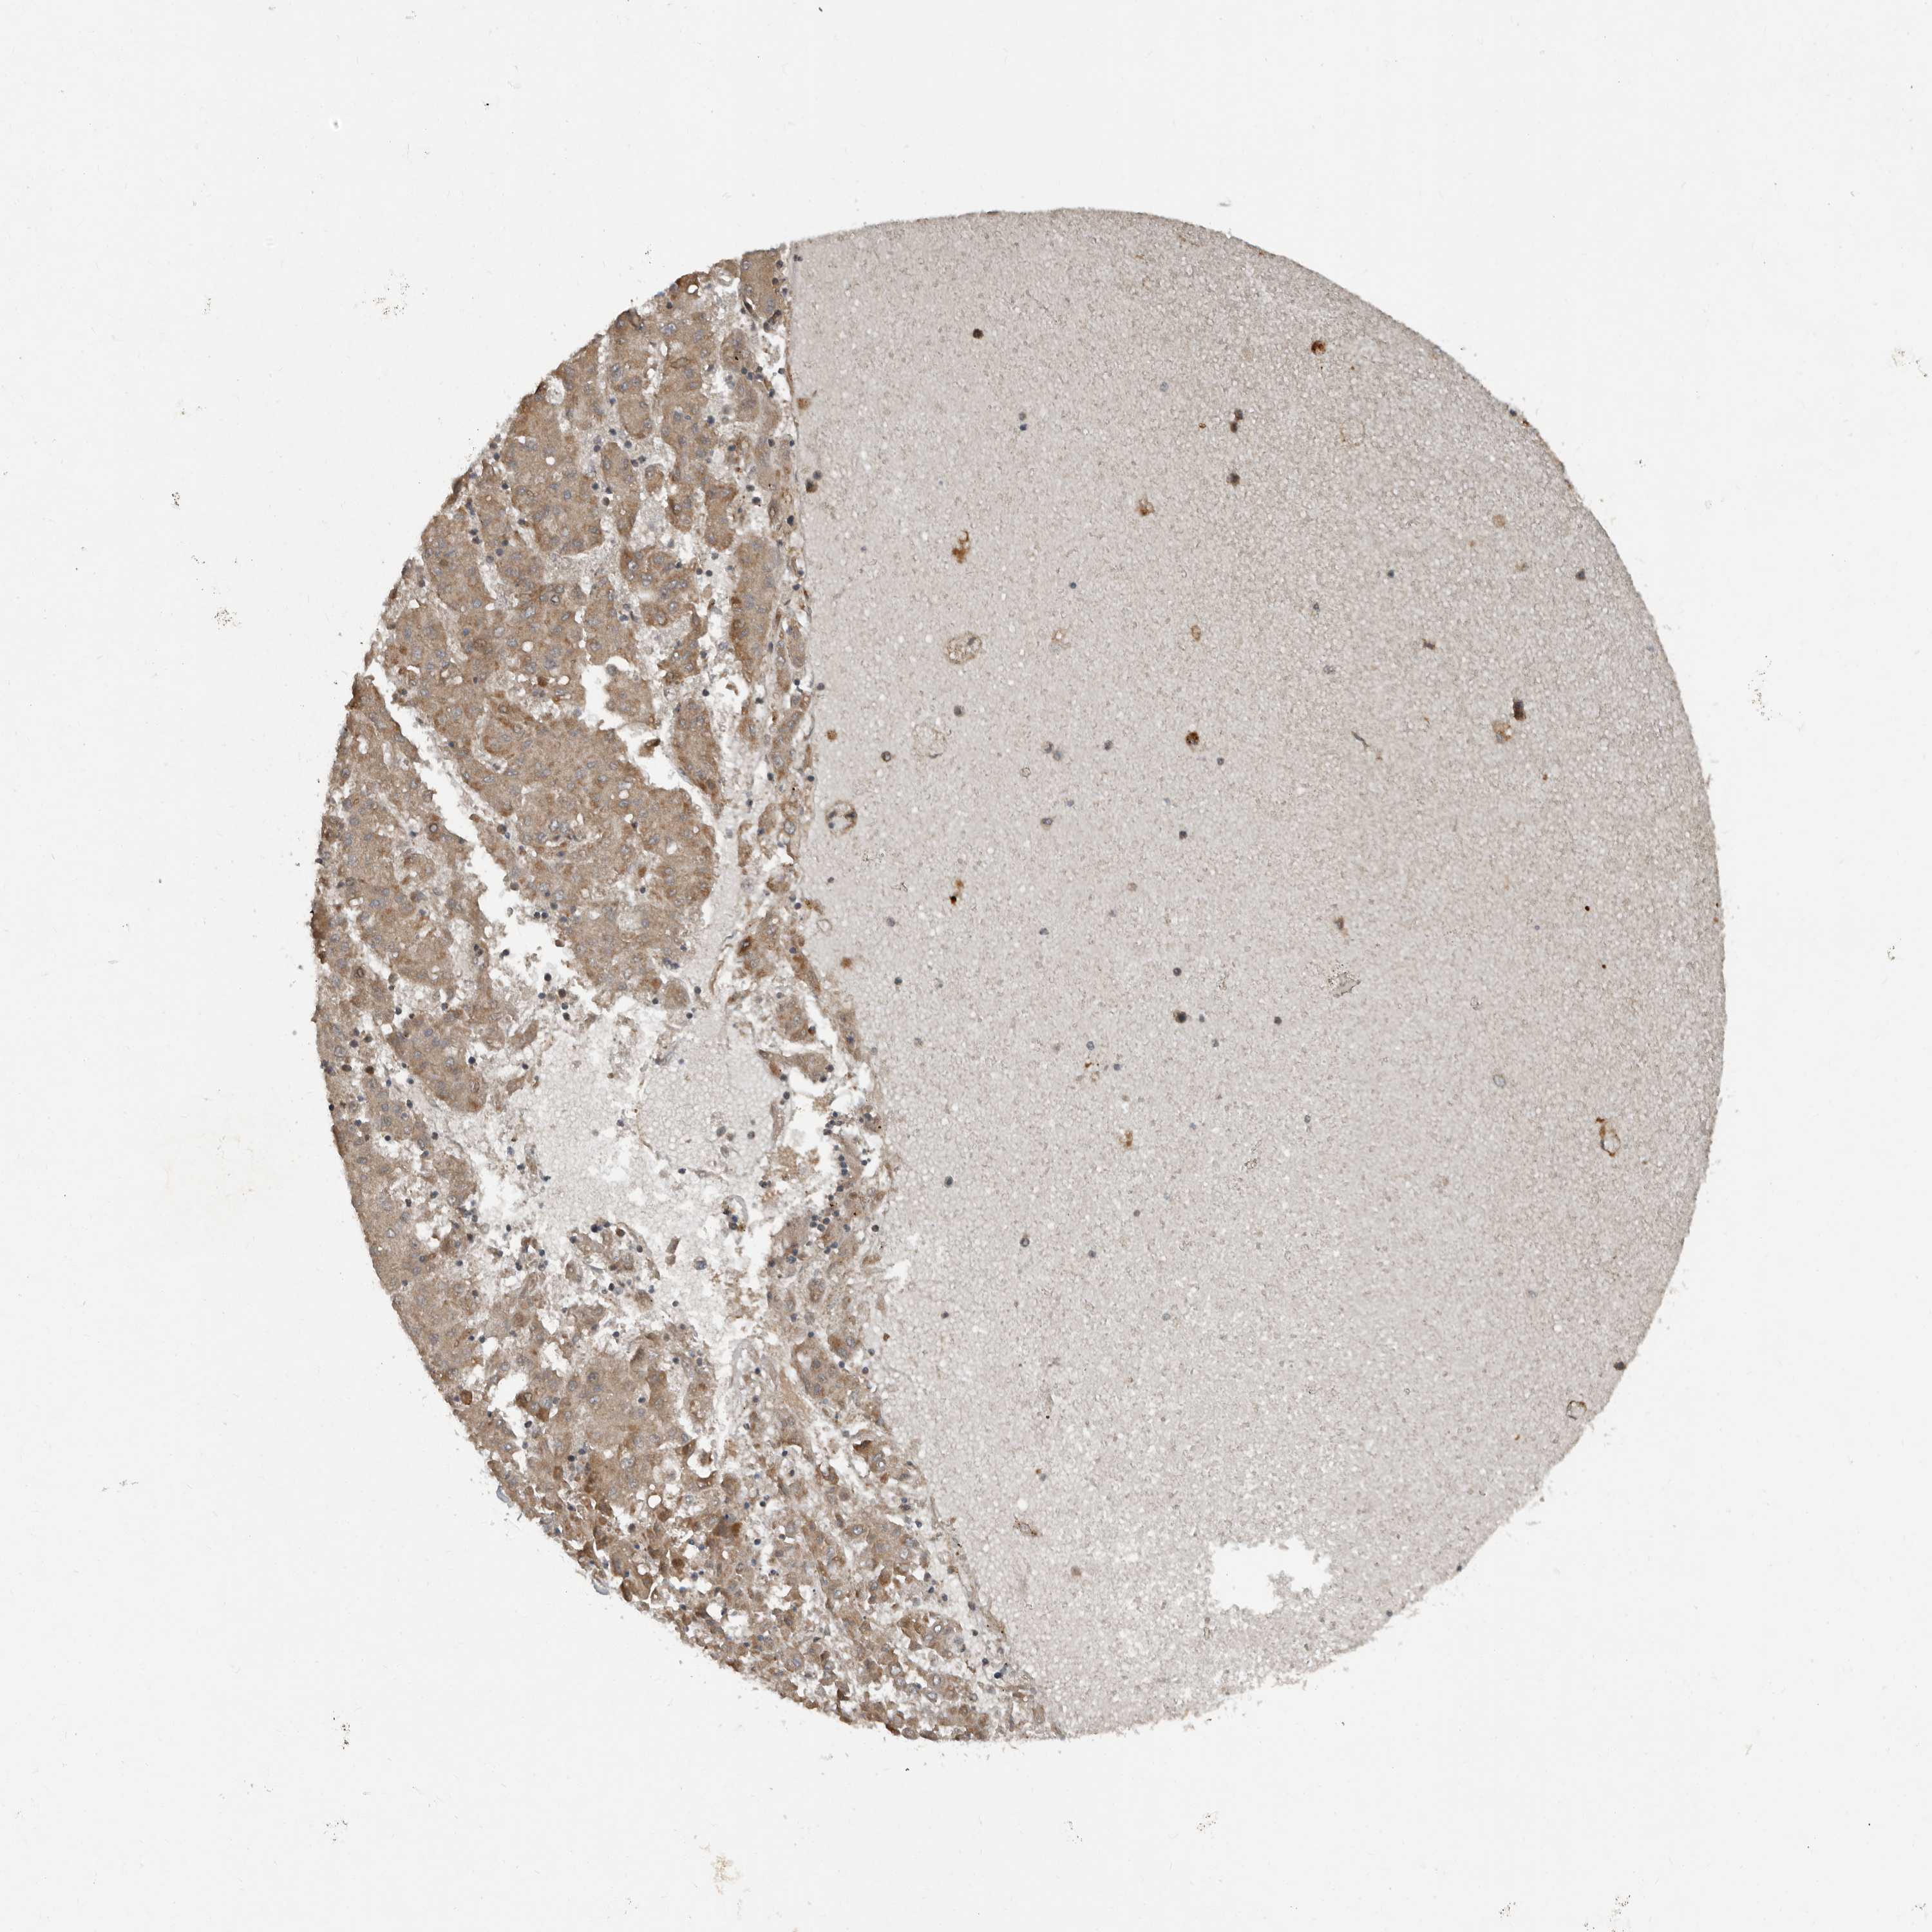

LIVER CANCER - Protein expressioni

A mouse-over function shows sample information and annotation data. Click on an image to view it in a full screen mode. Samples can be filtered based on level of antibody staining by selecting one or several of the following categories: high, medium, low and not detected. The assay and annotation is described here.

Antibody stainingi

Antibody staining in the annotated cell types in the current human tissue is reported as not detected, low, medium, or high, based on conventional immunohistochemistry profiling in selected tissues. This score is based on the combination of the staining intensity and fraction of stained cells.

Each image is clickable and will lead to virtual microscopy that enables deeper exploration of all samples and also displays staining intensity scores, fraction scores and subcellular localization as well as patient and tissue information for each sample.

Antibody HPA028907

Staining

High

Medium

Low

Not detected

Intensity

Strong

Moderate

Weak

Negative

Quantity

>75%

75%-25%

<25%

None

Location

Nuclear

Cytoplasmic/membranous

Cytoplasmic/membranous,nuclear

Cholangiocarcinoma

Carcinoma, Hepatocellular, NOS